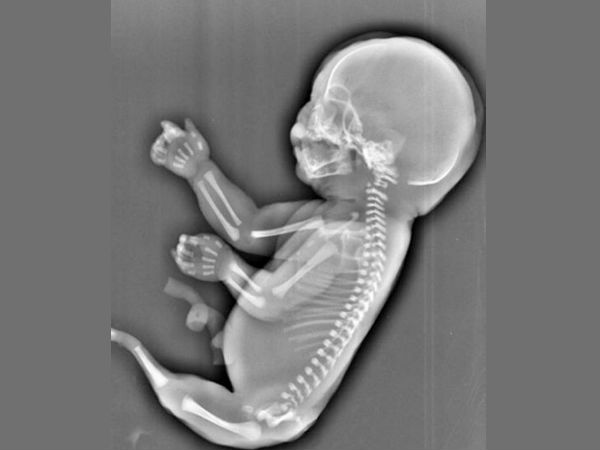

જાણો : ક્યારે પહેલી વાર ગર્ભમાં ભ્રૂણનું હૃદય ધબકે છે ?

જ્યારે અલ્ટ્રાસાઉંડનાં મૉનિટર પર બાળકનું હૃદય દેખાય છે અને ધબકારા ચાલતા રહે છે, પરંતુ એવી ઘણી બધી બાબતો ઝે કે જેની આપ કલ્પના પણ નથી કરી શકતાં.

આપ બાળકને જન્મ આપવાનાં હોવ, ત્યારે મોટાભાગની મહિલાઓ માટે માતૃત્વનો આ અહેસાસ પહેલી વખત અલ્ટ્રા સાઉંડ સાથે થાય છે.

ભ્રૂણની હાર્ટબીટ, પ્રેગ્નંસી, જન્મ અને બાદમાં આપનાં બાળકનાં આરોગ્યમાં મહત્વની ભૂમિકા ભજવે છે. એ સારી વાત છે કે આપનાં બાળકનાં હૃદયનાં ધબકારાને જોવાની ટેક્નિક ઘણી માહિતીઓ પ્રદાન કરે છે. સગર્ભાવસ્થા દરમિયાન બધુ બરાબર રહે અને જન્મજાત હૃદયની બીમારીઓનું વહેલી તકે જાણ થઈ જાય છે.

બાળકનું હૃદય :

શરુઆતમાં એક ટ્યૂબની સંરચના થાય છે કે જે એક ચૅમ્બર્ડ અંગમાં વિકસિત થાય છે કે જેનાથી આપણે વાકેફ છીએ. નિષેચનનાં થોડાક દિવસો બાદ તે વિકસિત થઈ જાય છે. અમે આપને આ અંગે કેટલીક માહિતી પ્રદાન કરી રહ્યાં છીએ.

ત્રીજુ અઠવાડિયુ : નિષેચનનાં 22 દિવસ બાદ ભ્રૂણનું હૃદય બનવાનું શરૂ થાય છે, પરંતુ તેના ધબકારા નથી સંભળાતા

પાંચમુ અઠવાડિયુ : ભ્રૂણનું હાર્ટ ચૅમ્બર વિકસિત થવાનું શરૂ થાય છે.

બાળકનું હદય :

છઠ્ઠુ અઠવાડિયુ : હાર્ટ રેટ 100-160 બીટ્સ પર મિનિટ (બીપીએમ) થઈ જાય છે. આ સમય આપ અલ્ટ્રાસાઉંડ મૉનિટર પર ધબકારા જોઈ શકો છો.

આઠમુ અઠવાડિયુ : હાર્ટ રેટ 170 બીપીએમ સુધી વધી જાય છે અને જન્મનાં સમયે 130 બીપીએમ પર લગભગ સ્થિર થઈ જાય છે.